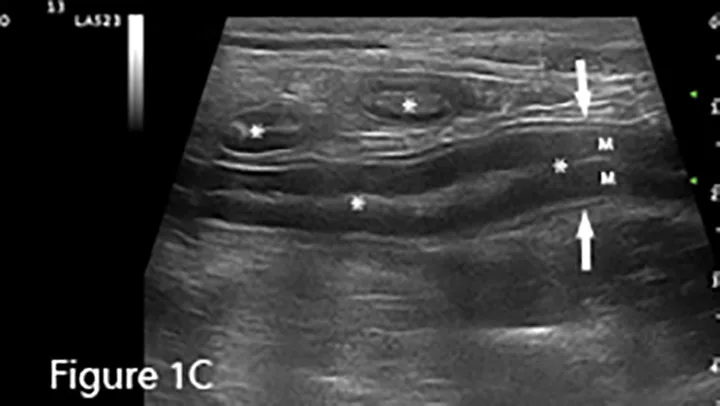

Sagittal ultrasound image of a canine duodenum (between arrows). The small intestine is usually empty or contains minimal fluid and/or gas (*). Bowel-wall layers are readily identified with the hypoechoic mucosal layer (M) being thickest, surrounded by thin submucosal (hyperechoic), muscularis (hypoechoic), and serosal (hyperechoic) layers. Transverse images of small intestine are present in the near field.